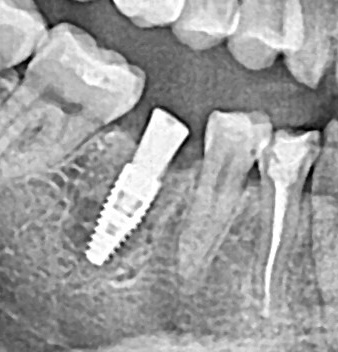

Ранее удаленный зуб 36 - незначительная атрофия по костным тканям и довольно выраженная атрофия по мягким тканям.

Имплант Straumann BLT 4.1*8mm SLActive - установлен в субкрестальное положение, произведено профилирование кортикальной кости системой Straumann Bone Profiler с целью создания более выгодного профиля прорезывания и исключения костной резорбции в области шейки импланта.

Чтобы компенсировать недостаточный объем мягких тканей проведена - мягкотканая пластика деэпителизированным соединительнотканным трансплантантом с неба.

Установлен заживляющий абатмент диаметром 6.5 мм.

Обратите внимание на объем и качество мягких тканей в области будущей финальной реставрации!

Финальная реставрация и диоксид циркония в полную анатомию методом раскрашивания.

Резюме:

Этот кейс мы с Сергеем смело относим к разряду простых - но, если посмотреть на него внимательно - здесь на каждом этапе есть определенные нюансы начиная от разреза и заканчивая финальной реставрацией.